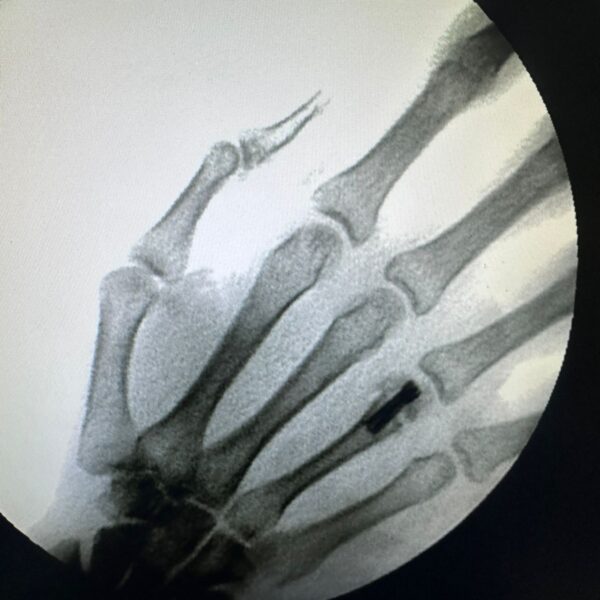

Moments That Mark Meaningful Recovery

Witness real patient transformations at The Ortho Clinic through images that reflect successful treatments and restored mobility.